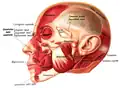

Position of buccinator muscle (red)

Position of buccinator muscle (red) -